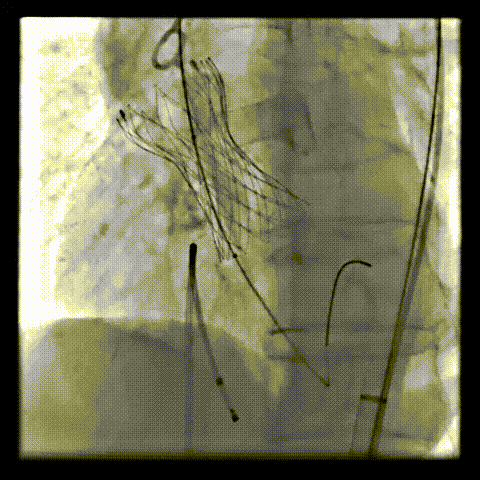

术中影像

根部造影可见返流;20mm球囊预扩,LCA灌注缝隙狭小

预置LCA保护;第一次释放,

团状钙化挤压导致瓣膜(AV23)少量下滑

回收后重新定位,第二次释放,

瓣膜(AV23)深度仍未达到最佳预期

完全回收,第三次定位释放,瓣膜(AV23)位置良好

瓣膜工作位释放“烟囱支架”;

瓣膜(AV23)完全释放后,“烟囱支架”后扩

最终造影,“烟囱支架”显影清晰,瓣膜形态及LCA灌注良好